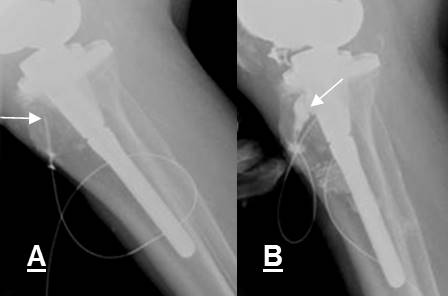

Fig 110. Salida material.

A: Rx AP y B: Rx lateral. Clavo endomedular, fijando una fractura del fémur. Hay ruptura en el tornillo, el cual está desplazado inferiormente.